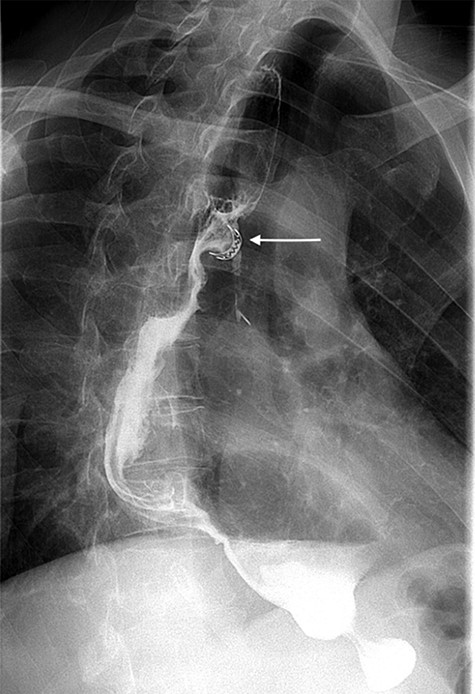

A 49-year-old male, with past medical history of tobacco smoking, who was diagnosed with adenocarcinoma of gastroesophageal junction underwent minimally invasive two-stage oesophagectomy. A month following discharge, he presented with complains of chest pain and persistent coughing (Ohno’s sign); barium swallow examination was conducted. This demonstrated a gastrobronchial fistula, between the newly formed gastric conduit and the left main bronchus (Figures 1 and 2). On endoscopic evaluation, a 5 mm communication between the tip of the gastric conduit and the left main bronchus with no evidence of ischemia and well-vascularised edges was noted.

Barium swallow demonstrating the gastric conduit (white arrow) and left bronchial tree (black arrow).

Lateral view of barium swallow demonstrating gastrobronchial fistula.